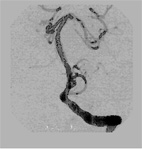

在所有此類病患中,基底動脈腦梗塞,不僅死亡率高達在第十八時以上,同時倖存的病患呈現重度昏迷狀態,且以往的治療方式有其侷限。本院在去年六月,成功的治療一位五十二歲正值黃金時節的壯年男性,將其完全阻塞的基底動脈,如下圖一及圖五。不僅有效的打通阻塞血管(國內外的文獻上尚無支架置放如此長度的報告),而且病患三個月後迅速恢復生活自理和相當程度的工作能力,使得團隊在腦中風全方位治療上,邁向新的里程碑。

圖一基底動脈完全阻塞

圖四還完全打通基底動脈血管